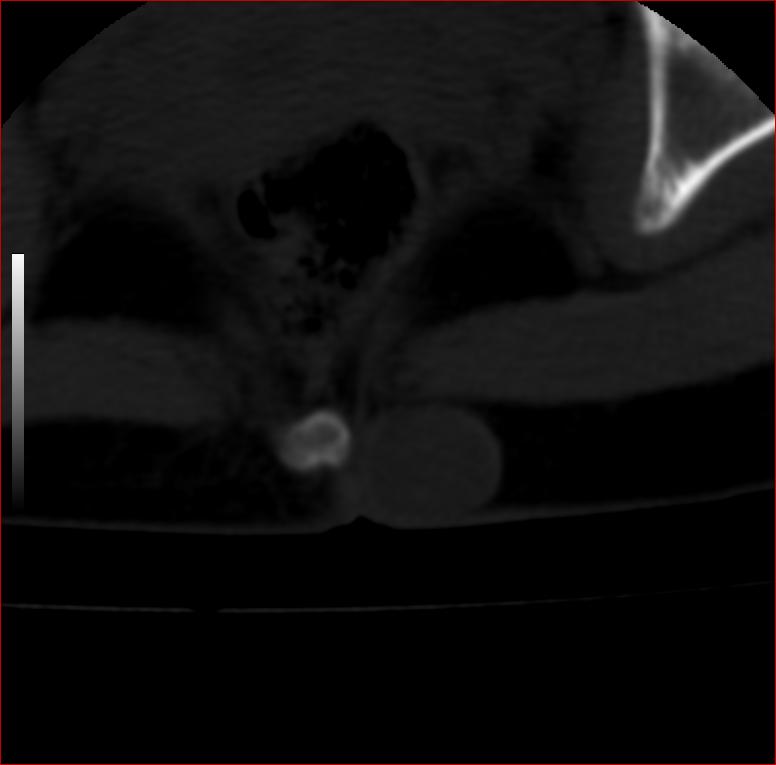

以下是引用13081830109在2007-5-16 18:51:00的发言:[br]良性病变[br]1.皮下皮脂腺囊肿[br]2.纤维瘤[br] 手术切掉就可以了

以下是引用zhangzhongshou在2007-5-16 18:21:00的发言:[br]皮下囊肿可能性大

以下是引用一个人在2007-5-16 20:35:00的发言:[br]1.皮下皮脂腺囊肿[br]2.纤维瘤[br]

以下是引用xulianj在2007-5-16 22:03:00的发言:[br]1皮下皮脂腺囊肿[br]2纤维瘤[br]3还需要除外发育畸形,如脊膜膨出。